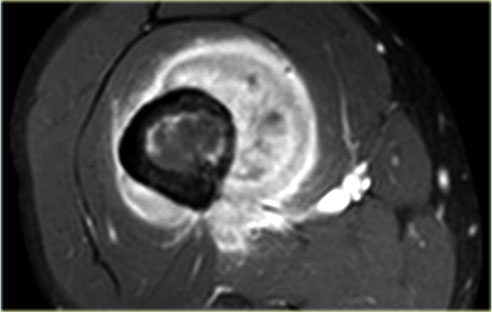

The images show a chondroblastoma in the patella.

Notice the extensive edema (blue arrow)